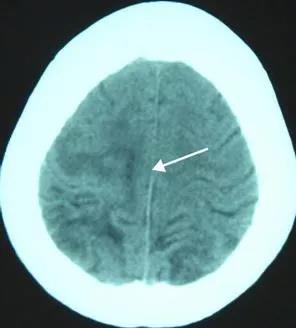

这一次,比在南昌好的是,终于查到了病因——父子两人其实并不是得了什么脑瘤,而是——中枢神经系统裂头蚴病。简单说,是一种寄生虫病,就是他们某次吃的青蛙里有一种叫裂头蚴的寄生虫进入了他们的身体,并随着血液进入了大脑,然后产生了如喷射状呕吐、抽搐、昏厥、癫痫等症状。

找到病因后,治疗相对来说就简单一些——做手术,将在脑子里的寄生虫取出来。于是,两个脑部手术,一下让我的邻居家成了赤贫状态,虽然邻里也会慰问一些,但终究杯水车薪。而最让人遗憾的是,手术后,脑部创伤是永久性且不可逆的,所以癫痫成为了他们伴随一生的痛。

严格说来,裂头蚴(plerocercoid)并不是一种寄生虫的名称。它是某些种类的绦虫在一个被称为“中绦期”的发育阶段的幼虫的总称。虽然还没有发育完全,裂头蚴在外形上已经与成虫颇为相似,而且由于运动能力很强,裂头蚴给寄生宿主带来的伤害常常要超过它们的成虫。裂头蚴一般寄居在蛙类和蛇类体内,爆炒也不会死,患病后可通过手术治疗,但术后依然会有症状性癫痫,经常突然倒地抽搐。

人体并非迭宫绦虫或是裂头蚴的适宜宿主,但它们却可以给人体带来很大的伤害。尤其是裂头蚴,能在人体不同部位间穿行,可能带来的损伤遍布全身。由裂头蚴引起的疾病统称为裂头蚴病,根据发病的部位,又可以大致划分为眼、皮下、口腔面部、脑和内脏五大类。在中国,眼裂头蚴病的发病率最高,症状也颇为恐怖,病人的眼部会出现肿块并伴随各种严重不适。如果裂头蚴侵入的部位是眼球,甚至可能导致失明。有时,裂头蚴会从患处“爬”出来,不少重口味故事中“眼睛里面爬出一条虫子”的情节大概就是源于这个症状。